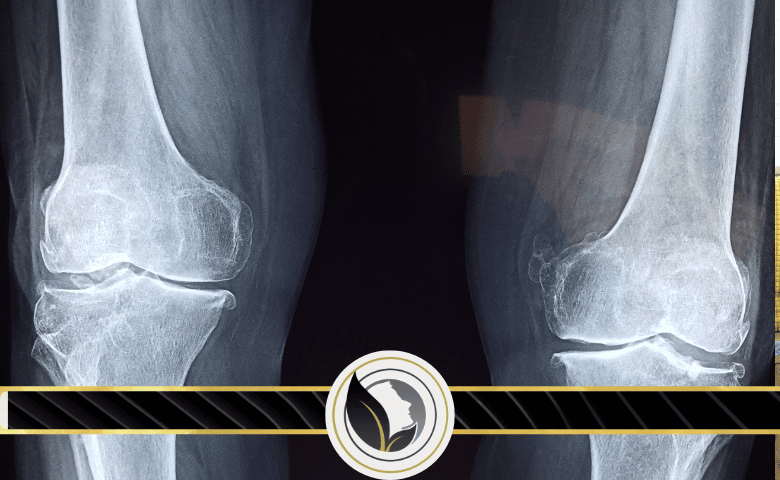

عملية التعظم هي تجديد العظام أو تكوّن مادة جديدة للعظام من خلال خلايا بناء العظم .

ومن الجدير بالذكر أن تلك العملية الحيوية تبدأ ما بين الأسبوعين السادس والسابع من التطور الجنيني، وتستمر تقريبًا حتى عمر الخامسة والعشرين، وفي حين أن ذلك قد يختلف بعض الشيء من شخص لآخر، ويجدر ذكر أن هناك نوعان من عملية التعظم، وهي ما تحدث داخل الغشاء وما تحدث داخل الغضروف، وكل عملية من تلك العمليات تبدأ بسلائف نسيج اللحمة المتوسطة، إلا أنها تختلف في كيفية تحولها إلى عظام.

إذ يقوم التعظم الغشائي بتحويل النسيج اللحمي إلى عظام وهو ما يُشكل العظام المسطحة للجمجمة والترقوة وغالبية عظام الجمجمة، أما التعظم الغضروفي فيبدأ في تحويل النسيج اللحمي إلى وسيط غضروفي، والذي يتم استبداله في وقت لاحق بالعظم كما يُشكل باقي الهيكل العظمي المحوري والعظام الطويلة.